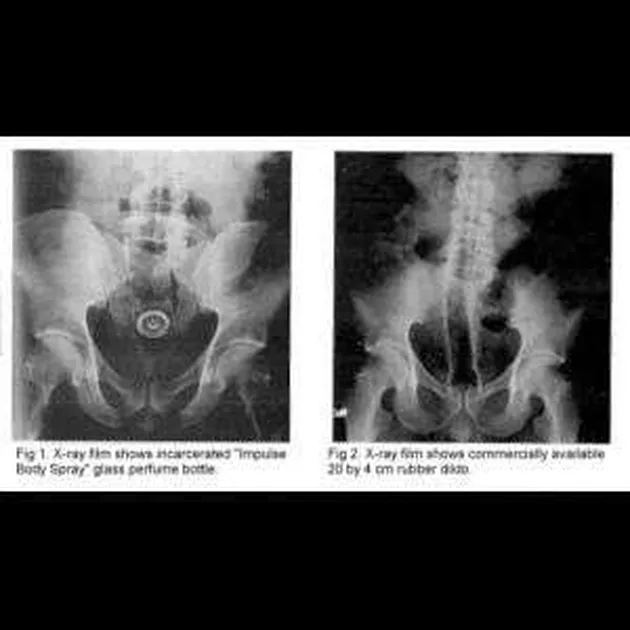

Seorang pengacara berusia 39 tahun mengakui jika dirinya memasukkan botol parfum ke dalam anusnya, dan tak bisa mengeluarkannya lagi. Botol parfum tersebut berdiameter 3 cm dan panjang 17 cm. Foto X-Ray ini tunjukkan bagaimana parfum tersebut 'nyempil' di tulang selangkanya.